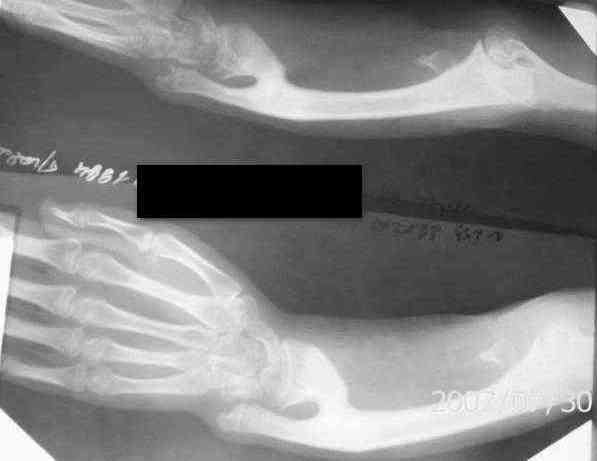

[Ortho] Лучевая косорукость у девочки 12 ти лет

Огромное спасибо за Ваше внимание .Функция кисти удовлетворительная,

просупинационные движения отсутствуют. Неврологических и трофических

нарушений не обнаружено.

По нашему мнению необходима коррекция деформации АВФ. ( выполнить

остеотомию лучевой кости у основания синостоза и проводить удлинение,

вторым этапомвыполнить коррегирующую остеотомию лучевой .